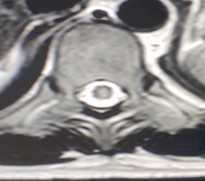

Se toman imágenes de control observando progresión de processo inflamatório a nível cerebral y a nível lumbar (figuras 4 y 5), progresión de siringomielia com afectación a nível cervical (figura 6)

Realce leptomeníngeo. Afectación de cisternas de la base

Figura 6